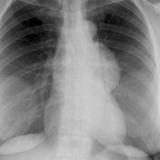

Case 9 Thymoma PA

Date: 04/04/2010

Views: 3172